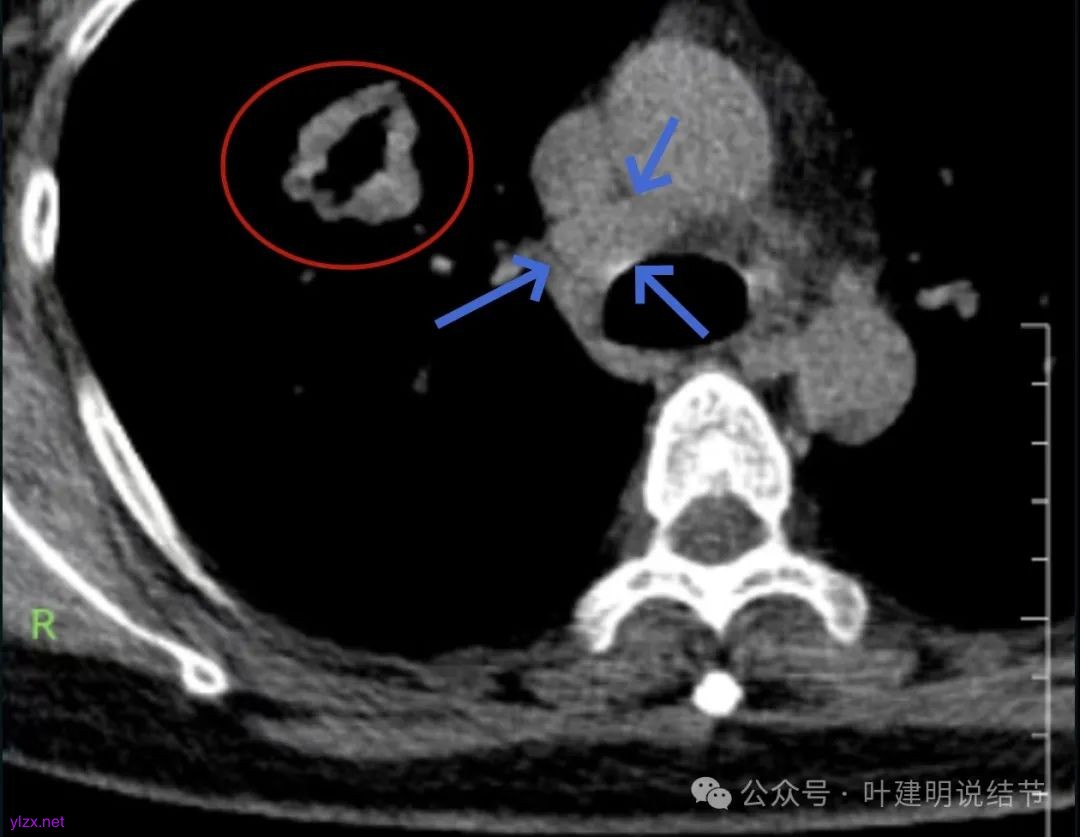

腔静脉旁明显肿大淋巴结。

你的右上叶这个病灶基本上肯定是肺癌,要尽快处理。从影像上看有以下特点:1、整体轮廓清楚,不似普通炎症的周围有晕或阻塞性改变;2、边缘明显的浅分叶,总体上的感觉膨胀性明显,不管哪个层面看上去都是鼓鼓的;3、边缘区域有磨玻璃成分而且也是分叶状的;4、部分层面见血管进入;5、空腔病灶的壁厚薄不均,内壁不光滑。我考虑中低分化肺癌,由于腔静脉旁有明显肿大淋巴结,需要进一步完善增强CT以及PET-CT检查以明确有无远处转移,是否仍可手术治疗(从病灶本身来说是可以肺叶切除治疗的)。要尽快处理。意见供参考!

这个病灶居然在国内顶级医院诊断为真菌感染?太意外了!有比这更典型的肺癌伴空洞的表现吗?给人的感觉肿瘤恨不得一夜之间占据整个上叶或胸腔的样子。我倒不担心诊断肺癌错了,而是怕恶性程度太高,还有没有手术机会,以及PET若没有远处转移仍能切除,切除后的远期效果会不会仍不好,大概率是低分化的病理类型。见识越多的病例,越发现一边是过度治疗盛行,一边是误诊也不鲜见,即便是大医院。